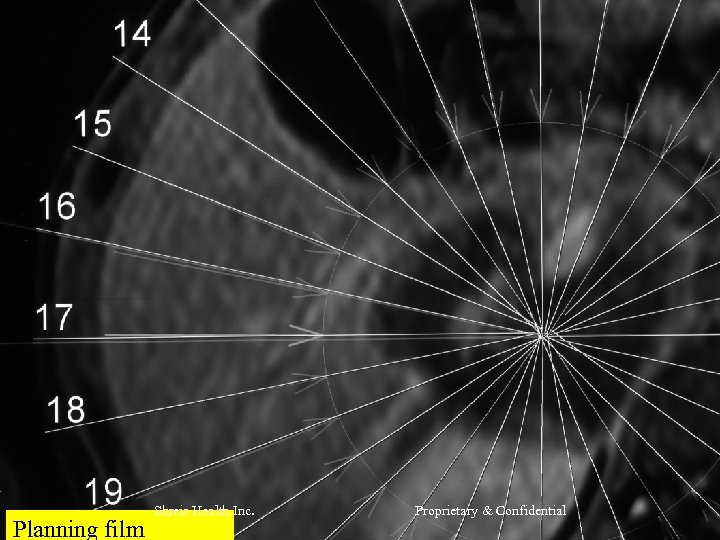

RFQMR Treatment Process l l l RFQMR treatment procedure starts with a conventional Diagnostic MRI. The Radiologist Prepares the Planning film positioning the RFQMR guns around the region of interest (ROI) He also does the surface marking of the ROI A template is made from the surface markings The Planning film is fed into the Cytotron Machine, that calculates the required dose. Thereafter the exposure continues for the determined period. Shreis Health Inc. Proprietary & Confidential

Planning film Shreis Health Inc. Proprietary & Confidential

Typical Dose Planning Process • The Gun emission depends on the tissue that come in the gun path. • Air is the best friend and Fat is the worst enemy of RFQMR. • PD or Proton Density is simply the H 2 atom concentration in a given tissue. Shreis Health Inc. Proprietary & Confidential